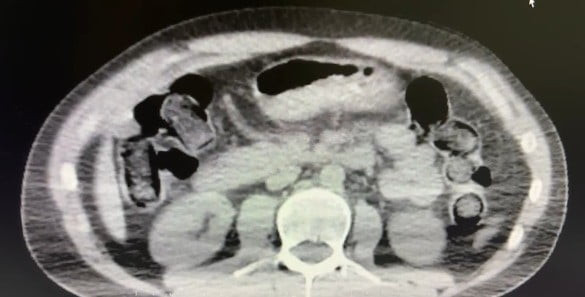

Şüphelilerin ikametgahlarında ve araçlarında yapılan aramada 101 kapsül halinde 722 gram uyuşturucu madde, 1 adet hassas terazi, uyuşturucu sevkiyatında yutma yönteminde kullanılan çeşitli materyaller ile birlikte 20 bin 210 TL, bin 320 euro ve 10 ABD doları ele geçirildi.